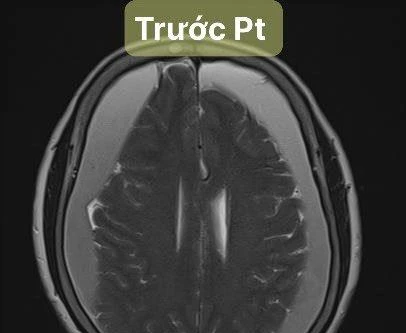

Khoan sọ hút máu tụ dưới màng cứng hai bên bán cầu cứu sống cụ bà 82 tuổi ở Hà Nội